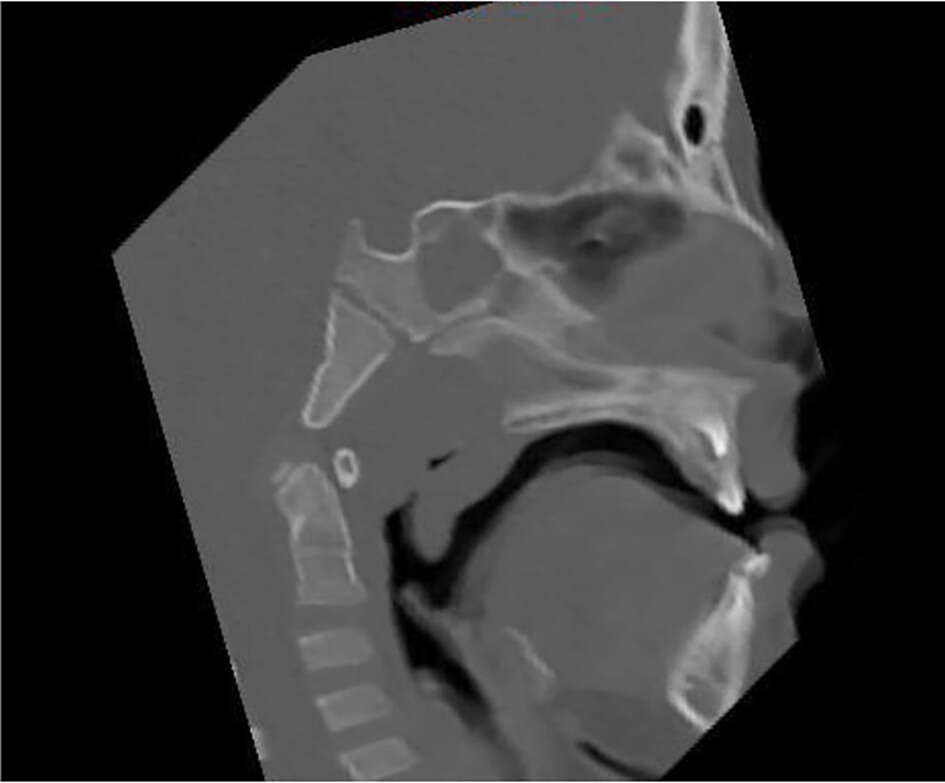

Tale studio permette di approfondire determinati aspetti morfologici predisponenti alle OSAS, come particolari caratteristiche occlusali e craniofacciali12, ipertrofia adenotonsillare, anchiloglossia, deglutizione atipica ecc. Per un completo studio del caso viene richiesta, infine, l’esecuzione delle seguenti radiografie: l’ortopantomografia, la teleradiografia in proiezione latero-laterale e, in particolari situazioni cliniche, la CBCT per uno studio più approfondito delle vie aeree superiori (Figura 3).

Numerosi studi sono a sostegno dell’efficacia del trattamento con espansore rapido del palato14 (Figura 3) nell’aumentare il volume nasale e incrementare il flusso respiratorio15.